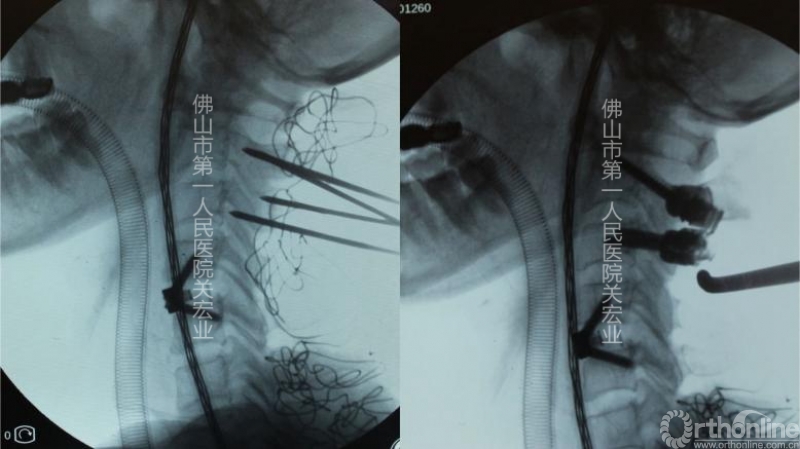

术中操作:

导板与模型

手术视频

术中置钉与定位